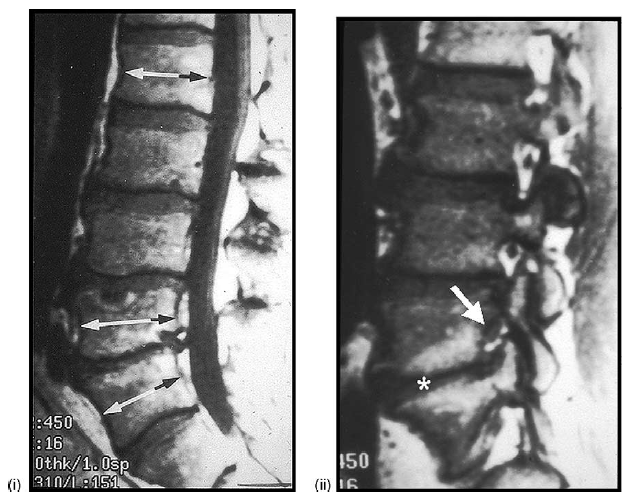

(i) parasagittal T1-weighted MRI showing collapse of the L5-S1 disk (asterisk) and superoinferior narrowing of the spinal neural foramen (arrow: compare with (A)).

(ii) Parasagittal T2-weighted fat-suppressed MRI showing the posterior spinal facet (zygapophyseal) joint effusion (arrows: compare with (A)).

(iii) Parasagittal CT reconstruction showing the collision of the superior facet process (asterisk) with the overlying pars interarticularis-pedicle junction (dot), and the minor associated osteophytosis (arrow)

(iv) Parasagittal CT reconstruction showing the bony excavation/erosion of the undersurface of the pars interarticularis at the L4 and L5 levels (arrows).

(v) Parasagittal CT reconstruction showing truncation of the tip of the superior articular facet process of S1 (arrow: compare with (B) and the sharp, pointed termination of the superior articular process at the L4-L5 level above: arrowhead).

(vi) Parasagittal T1-weighted MRI showing again the truncation of the tip of the articular facet process (asterisk) of S1 (compare with (B)).